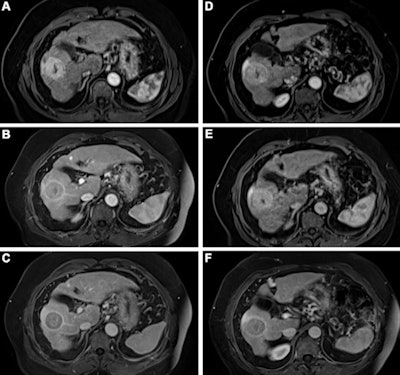

Contrast-enhanced MRI of the liver after administration of gadopiclenol (0.05 mmol/kg) and gadobutrol (0.1 mmol/kg). Axial 3D T1-weighted dynamic contrast-enhanced MRI scans during the (A, D) arterial, (B, E) portal venous, and (C, F) delayed phases in a 66-year-old man with hepatocellular cancer. Images were obtained after administration of gadopiclenol at 0.05 mmol/kg (in A, B, and C) or gadobutrol at 0.1 mmol/kg (in D, E, and F).The investigators found that gadopiclenol at half the dose of gadobutrol performed comparably for all qualitative visualization parameters and for all readers. The majority of readers across the three groups (ranging from 75% to 83%) reported no preference between the two agents for image quality.